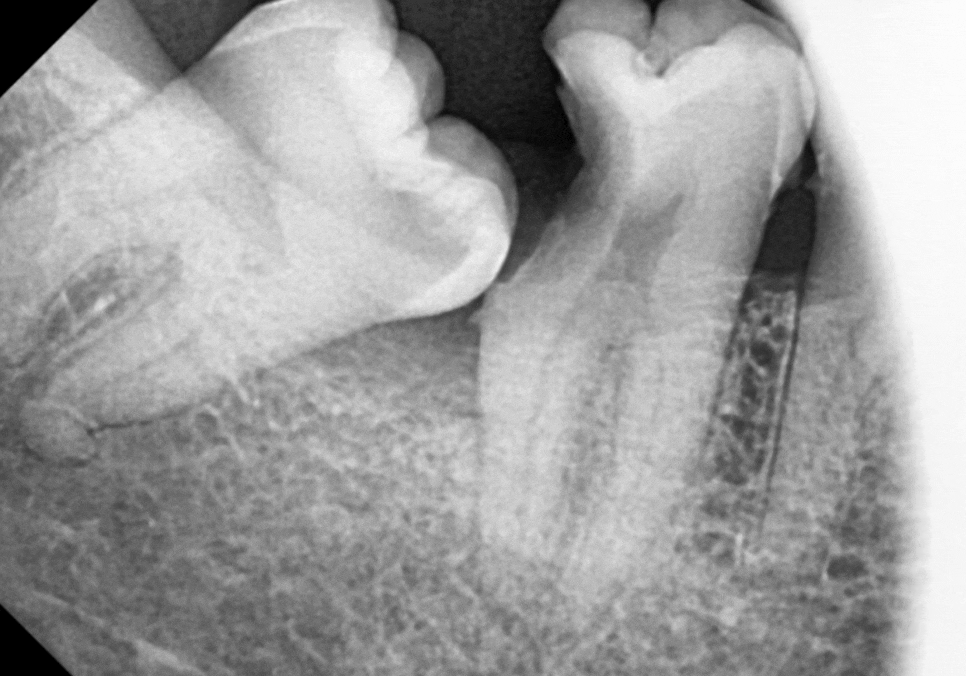

치과 의사로서 최대한 자연 치아를

살려보고 싶었지만,

충치가 이미 잇몸 라인

아래 뿌리 쪽까지 진행되었고,

사랑니 잇몸 틈새로 생긴 만성염증으로

뼈가 녹아 있는 상태였습니다.

결국 발치를 결정할 수밖에 없었죠.

사랑니와 그 앞 치아까지 모두 발치 후

임플란트로 진행하기로 했습니다.